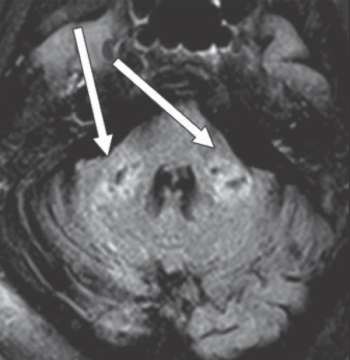

CT Colonography & Tumor Differentiation; COVID-19 & Leukoencephalopathy; MRI, the Angiography Suite, and Acute Ischemic Stroke; Plus, DBT, African American Women, & Decreased Access

Mammography "Sweet Spot" Recall Rate; MRI for Early-Stage Testicular Cancer Follow-Up; COVID-19 and Body Self-Attack; Plus, Global Radiology